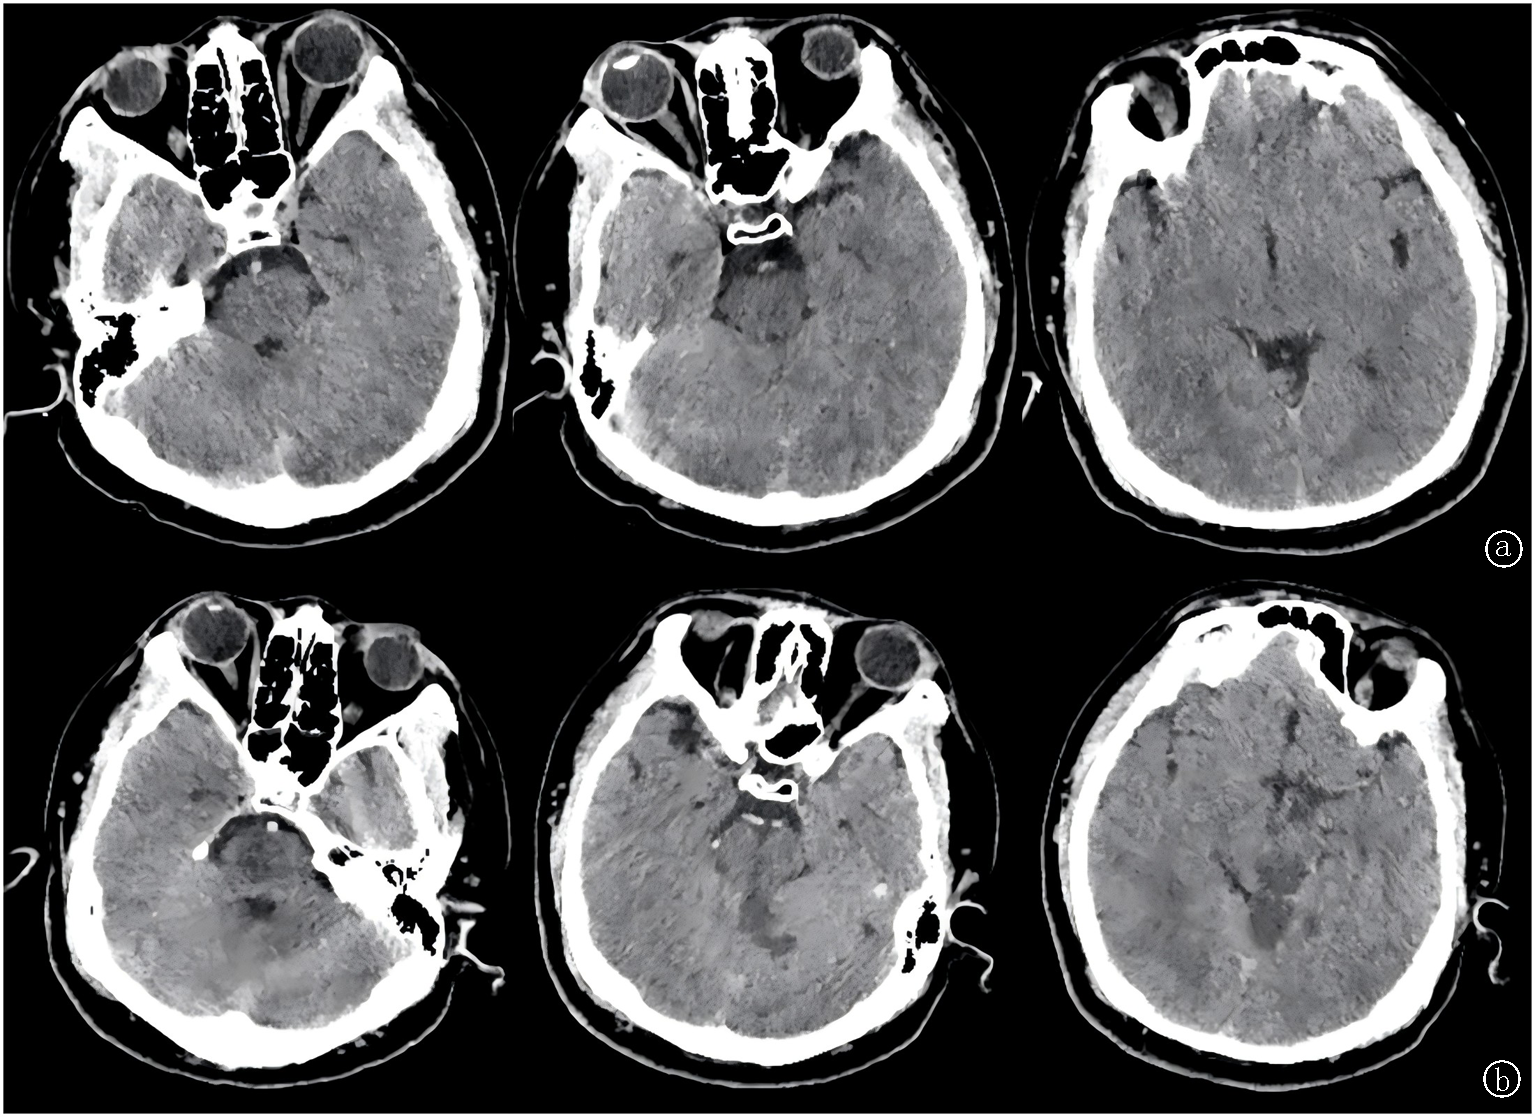

Fig.1 Changes of lesions a. On December 25, 2023, the patient's emergency head CT showed no brain parenchymal lesions; b. On December 26, 2023, the patient's head CT reexamination showed that the low-density shadow of bilateral thalamus, pontine and cerebellum was consistent with the distribution of posterior circulation vessels